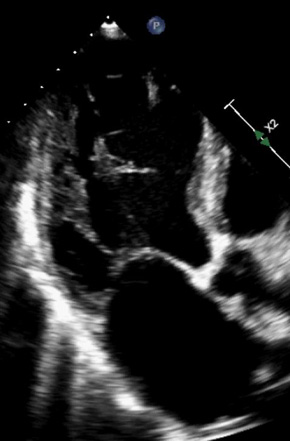

Die Reduce-MFA-DZHK-25 Studie ist eine prospektive, randomisierte, kontrollierte, offene, multizentrische Parallelgruppenstudie mit verblindeter Outcome-Analyse, in der die antifibrotische Wirksamkeit der Medikamente Spironolacton und Dihydralazin bei Patientinnen und Patienten mit Aortenstenose und ausgeprägter Myokardfibrose, die einen kathetergestützten Aortenklappenersatz erhalten, mittels MRT untersucht wird.